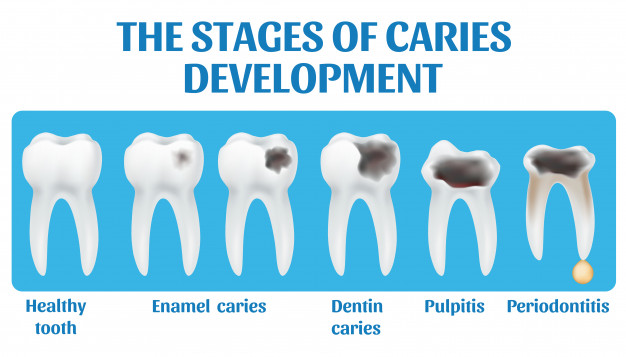

Caries (oftewel gaatjes) - Tandartspraktijk Stedent

Hoe ontstaan gaatjes in |

Gaatjes in tanden en kiezen - Amstelveen

Cariës (gaatjes) - Saentower

| Cariës, wat is het en hoe is het te voorkomen?

Hoe ziet een gaatje en hoe herken je ze? - Tandarts Jordaan

Cariës /

Hoe ziet een gaatje eruit? Zo herken je in de tanden en kiezen!

Alles over gaatjes in kiezen en - De